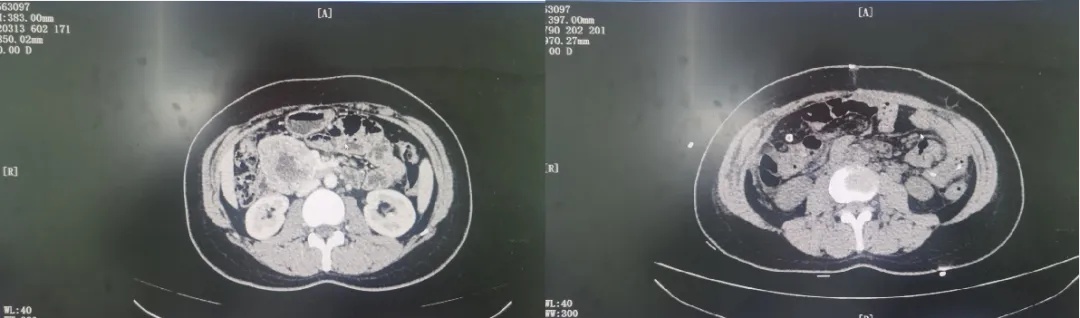

经急诊胃镜发现,该患者为腹膜后肿瘤侵犯十二指肠导致消化道大出血,血色素仅4g,预计出血量2000ml,内镜下止血困难。该院消化内科迅速联系外一科(胃肠外科)朱光辉主任,立即启动急救流程。

朱光辉主任凭借多年经验,术中准确探查,发现大小约8cm的腹膜后肿瘤侵犯十二指肠,按照既定手术方案,顺利完成腹膜后肿瘤切除联合胰十二指肠切除术。在麻醉科保驾护航下耗时5小时顺利完成手术,解除了这颗“定时炸弹”。